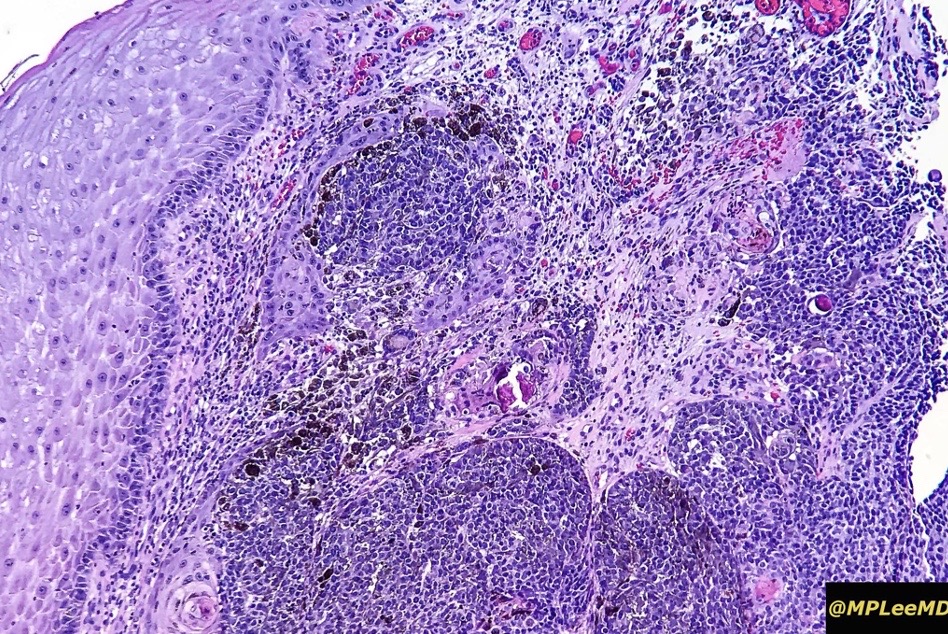

An exceedingly rare collision tumor composed of an admixture of squamous cell carcinoma/basal cell carcinoma/trichoblastoma respectively and melanoma. Although most appear to have behaved in a benign fashion, a malignant basomelanocytic tumor is illustrated below. More cases will be need to be stidies/published before the true biological behavior of this group of tumors can be satisfactorily elucidated. I think that complete excision should be the rule and a careful follow-up recomended.

•Sun-damaged skin of head & neck presenting as a keratotic papule or nodule

•Most cases appear to be indolent but a rare malignant basomelanocytic tumor example has been documented

Basomelanocytic tumor

Squamomelanocytic tumor